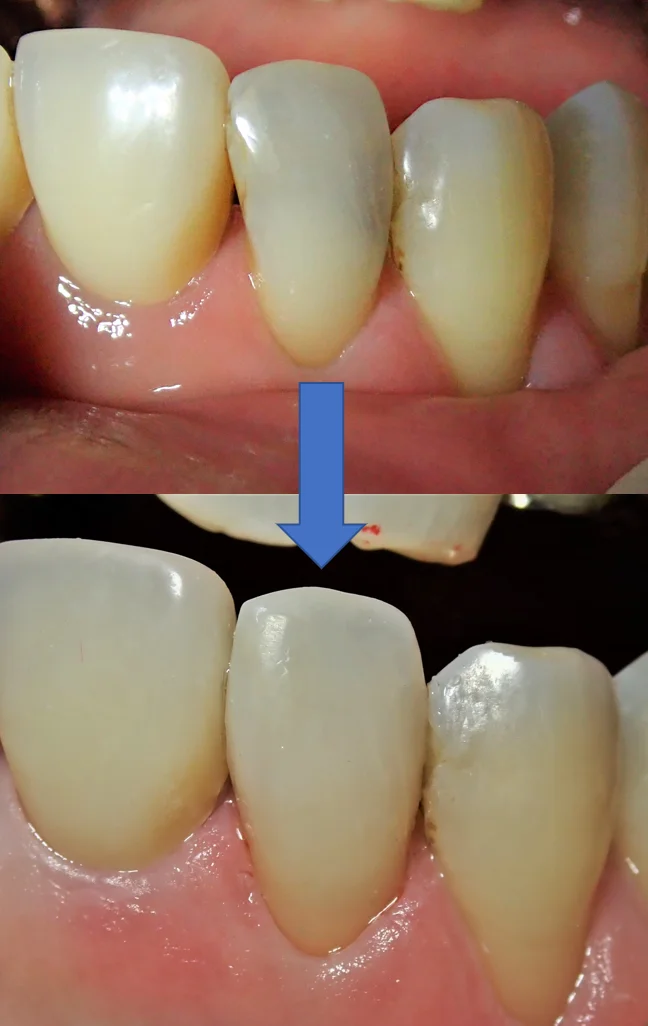

最後に術前術後の写真を載せて終了したいと思います。

表側がこんな感じで

裏側がこんな感じです。

本来なら全周削って被せる「クラウン」形態になるような状況でしたが、無事に歯質を多く温存できたかと思います。